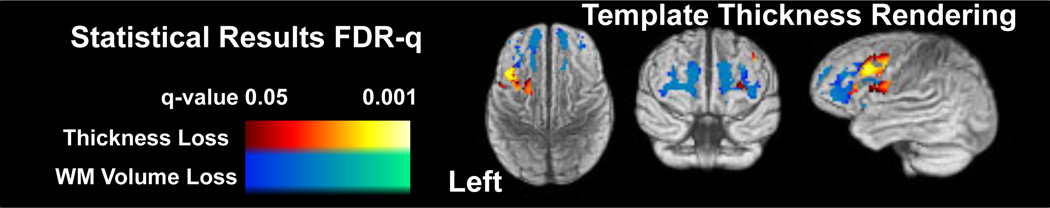

Given the results of Evaluation 1 and 2, we test whether SUAAV is able to detect neurobiological effects of dementia expected to occur within the frontal and/or temporal lobes, as in FTD. Thus, the full SUAAV pipeline (with SCCAN) is used to process 26 FTD subjects and 7 elderly subjects. The SCCAN variable selection is used to restrict the ANCOVA test that uses a model of the form: Thickness Change ≈ x0 + age + gender + diagnosis. The same model is used for the Jacobian. The p-values associated with the diagnosis predictor are corrected by the false discovery rate and shown, rendered on the template cortex, in figure 3. Middle frontal gyrus (MFG) and inferior frontal gyrus (IFG) on the left survives correction, along with anterior frontal lobe white matter. To eliminate the possibility that misregistration led to these results, we also interrogated the average thickness change across the MFG and IFG regions gained from the parcellation. These regional measures—which do not suffer from interpolation or registration error—also showed significant reduction over time in FTD relative to controls, thus affirming our voxel-wise findings.

Fig. 3.

The SUAAV method provides a restricted set of regions over which to perform statistical testing. Results are FDR corrected where we accept q-value (corrected p-value) < 0.05 as significant with cluster size > 100 mm3. Left frontal cortex atrophies at a greater rate (approximately 6–10 % per year) in FTD than controls. The template labeling identifies the cortical regions as middle frontal and inferior frontal gyrus. The white matter loss occurs bilaterally in the anterior frontal lobe. These findings are consistent with what is known about frontotemporal dementia.